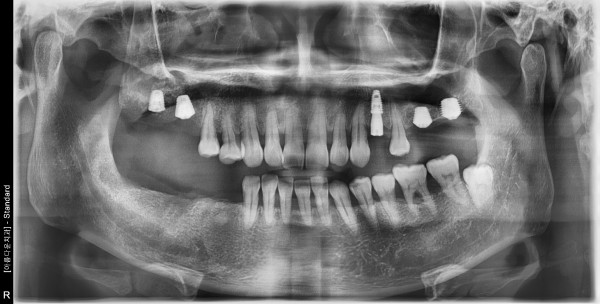

44세 남자환자 / 우측 하악 임플란트식립 (완성)